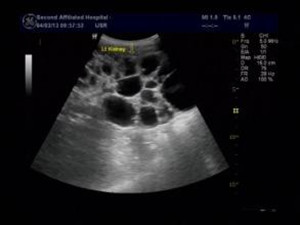

什么是充满性胆结石:

胆囊是储存胆汁的场所,但是因为胆汁中某些成分的改变可能会出现胆囊结石。而胆囊结石的个数可以是一个或者数个,所以当结石的个数很多,体积很大,使得胆囊的囊腔被结石全部占据时,就是我们所说的充满型胆结石。>>>点击了解有哪些形成原因与症状